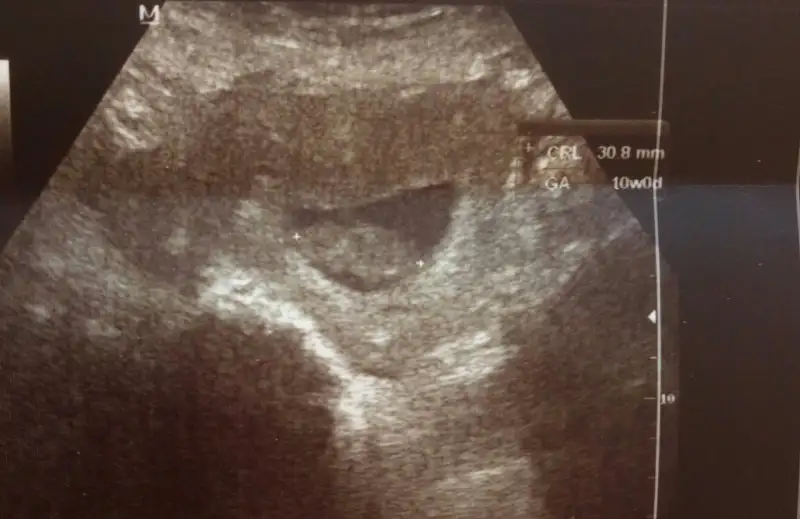

Toksoplazma testini vermeden doktorumuz kıyak geçti de ultrasona aldı.

3 cm olmuşuz!

Maaşallah annesi, kocaman olmuş.

Bir de ne kadar tombik duruyor, nazar değmesin.

Doktor tombik demedi de, fazla hareketli cinsiyetini zamanında bile göstermeyebilir dedi sorduğunda.